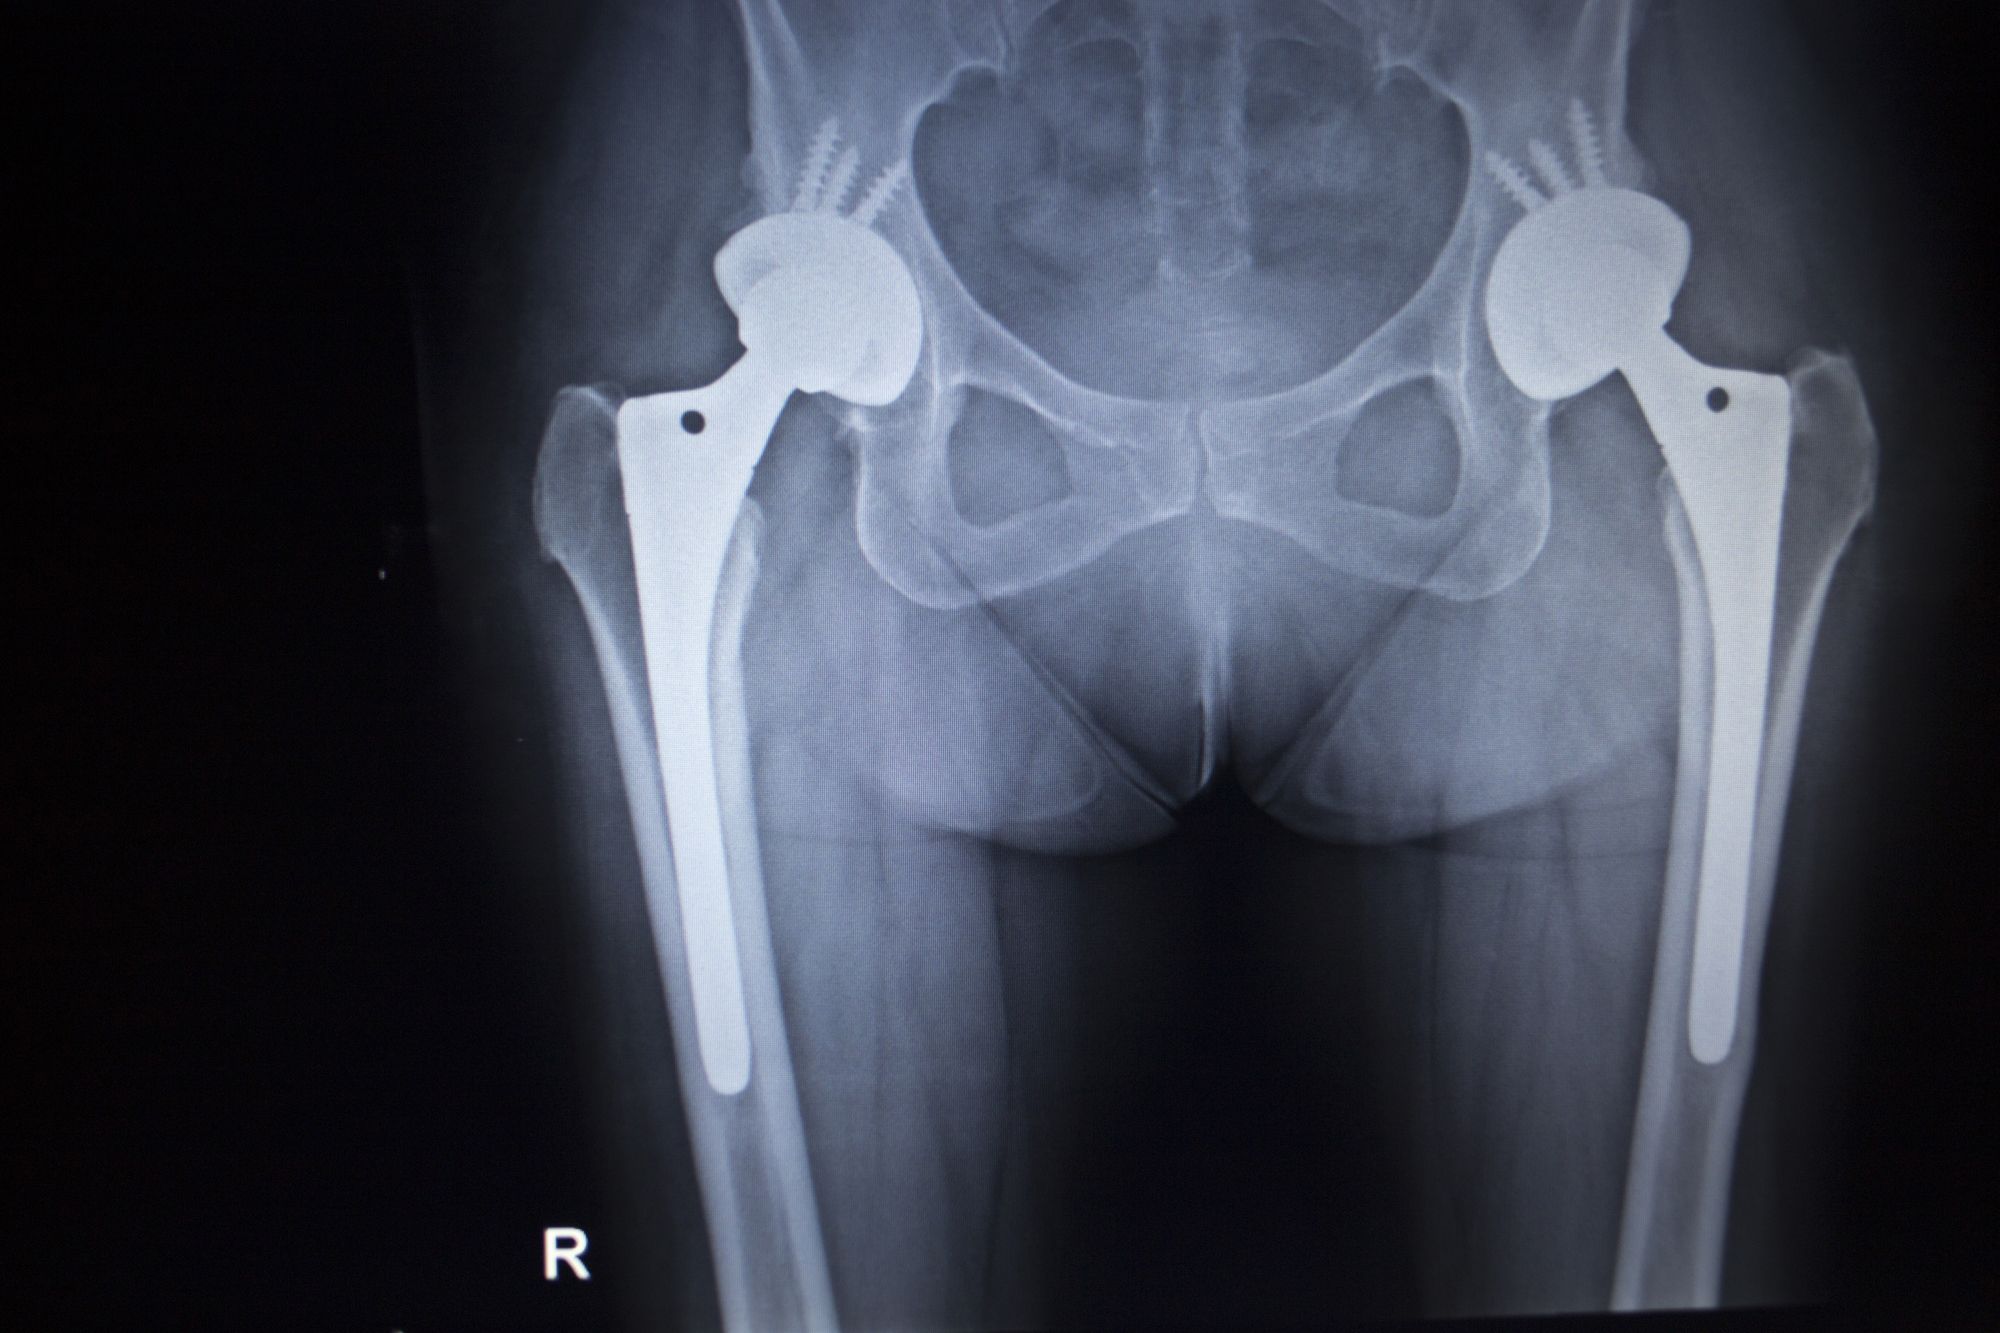

What Brand Of Hip Replacement Is Being Recalled . From 2002 to 2013, consumer's union. in june 2021, exactech recalled some gxl liners for novation, acumatch, and mcs hip replacement. Remove from inventory, all synovo total. the fda is getting the word out regarding a recall effort from zimmer biomet related to its discontinued cpt hip. the fda reminded healthcare providers and patients on thursday that several exactech joint replacement. do not purchase or implant the currently available synovo total hip system. irby is one of more than 1,100 patients suing exactech after it began recalling artificial knees, hips, and ankles,. causes for hip replacement recalls include design flaws, early implant failure and migration issues.